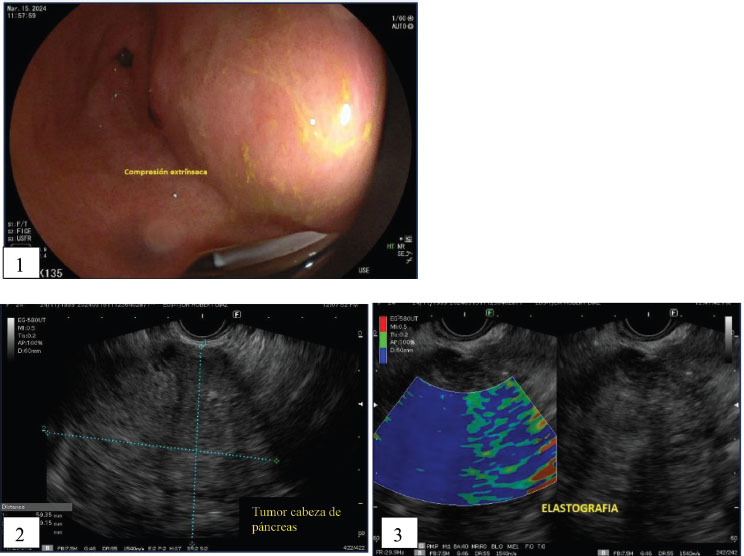

Se trata de una paciente femenina de 24 años, sin antecedentes mórbidos conocidos, con historia de dispepsia, náuseas y signos de obstrucción de la salida gástrica. Es referida al servicio de cirugía general por el departamento de gastroenterología debido a la presencia de un tumor de gran tamaño, de 69x59 mm de diámetro, en la cabeza del páncreas, que desplazaba el estómago y el duodeno, identificado mediante ultrasonografía endoscópica (Figura 1-3), con varios meses de evolución. Los hallazgos imagenológicos evidenciaron una lesión solidoquística irregular e hipoecogénica, en el cuerpo y parte de la cabeza del páncreas. Se observó infiltración en la curvatura menor del estómago y el peritoneo adyacente, acompañada de múltiples adenopatías mesentéricas. Su examen físico presenta un abdomen semi-globoso, dolor en nasogástrico a la palpación, peristalsis adecuada, depresible, no masas palpables, no visceromegalia valorable. Dada la presentación clínica y radiológica, la decisión sobre el manejo diagnóstico invasivo no fue tomada en consideración, por lo que, en este caso, no se realizó una biopsia de la lesión antes de la intervención quirúrgica. Los resultados de laboratorio preoperatorios fueron normales, incluyendo hemograma, función hepática y marcadores tumorales como CA19-9, que se encontró dentro de los rangos de referencia.

Figuras 1-3. En figura 1 se aprecia la comprensión extrínseca del tumor en la cabeza del páncreas. En figuras 2 y 3 se evidencia la lesión hipoecogénica, irregular, de 69 x 59 mm de diámetro, con elastografía predominante azul sugestivo de tumor de consistencia dura. (Ultrasonografía endoscópica)